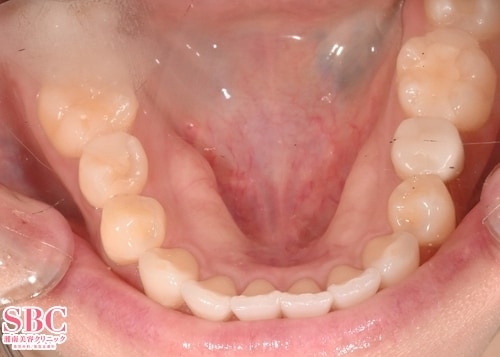

施術前

アーチが全体的に広がっており歯が前に出ている印象